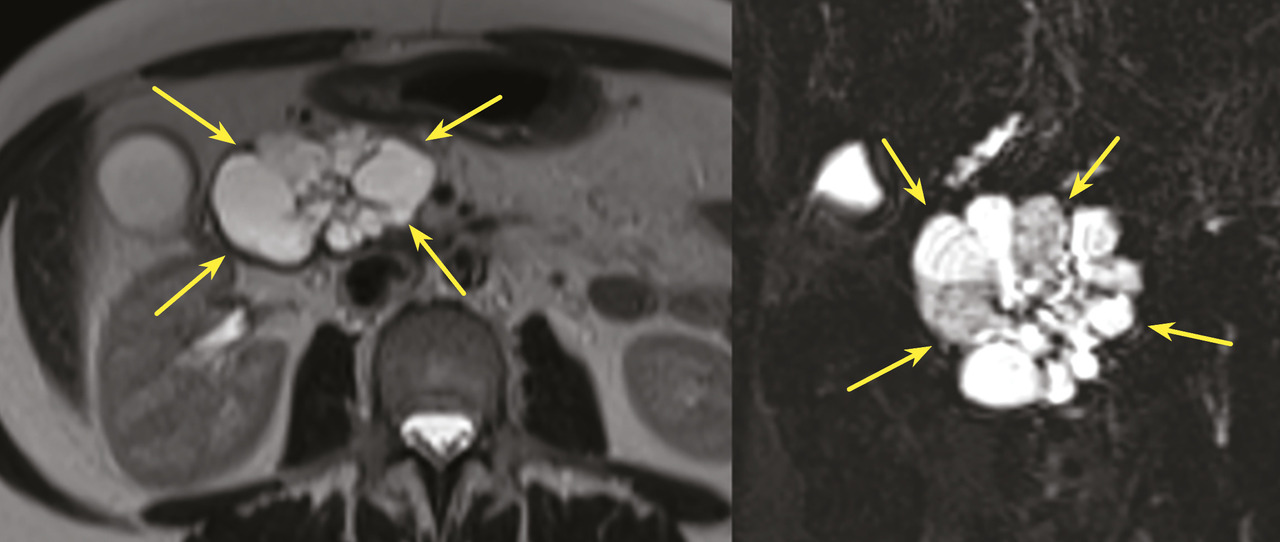

Les TIPMP sont des lésions canalaires intra-épithéliales développées aux dépens des canaux pancréatiques (principal ou/et secondaires) [fig. 1]. Elles prédominent au niveau de la tête et du crochet, mais peuvent concerner toute la glande. La composante kystique des TIPMP présente un épithélium de type mucineux avec production de mucus. Au cours du processus d’oncogenèse, des papilles commencent à se former, et différents phénotypes cellulaires distincts ont été décrits, corrélés à leur pronostic.

Toujours parmi les LKP rares à potentiel malin, on compte les tumeurs neuro-endocrines (TNE) kystiques (20 % des TNE pancréatiques) [fig. 5]. De découverte fortuite et non fonctionnelles, les TNE kystiques sont uniques, uniloculaires, bien différenciées, de bas grade, c’est-à-dire avec un indicateur de prolifération Ki67 < 3 %, et la présence d’une masse hypervasculaire (nodule) au niveau de la paroi. La partie charnue tissulaire peut être de petite taille.